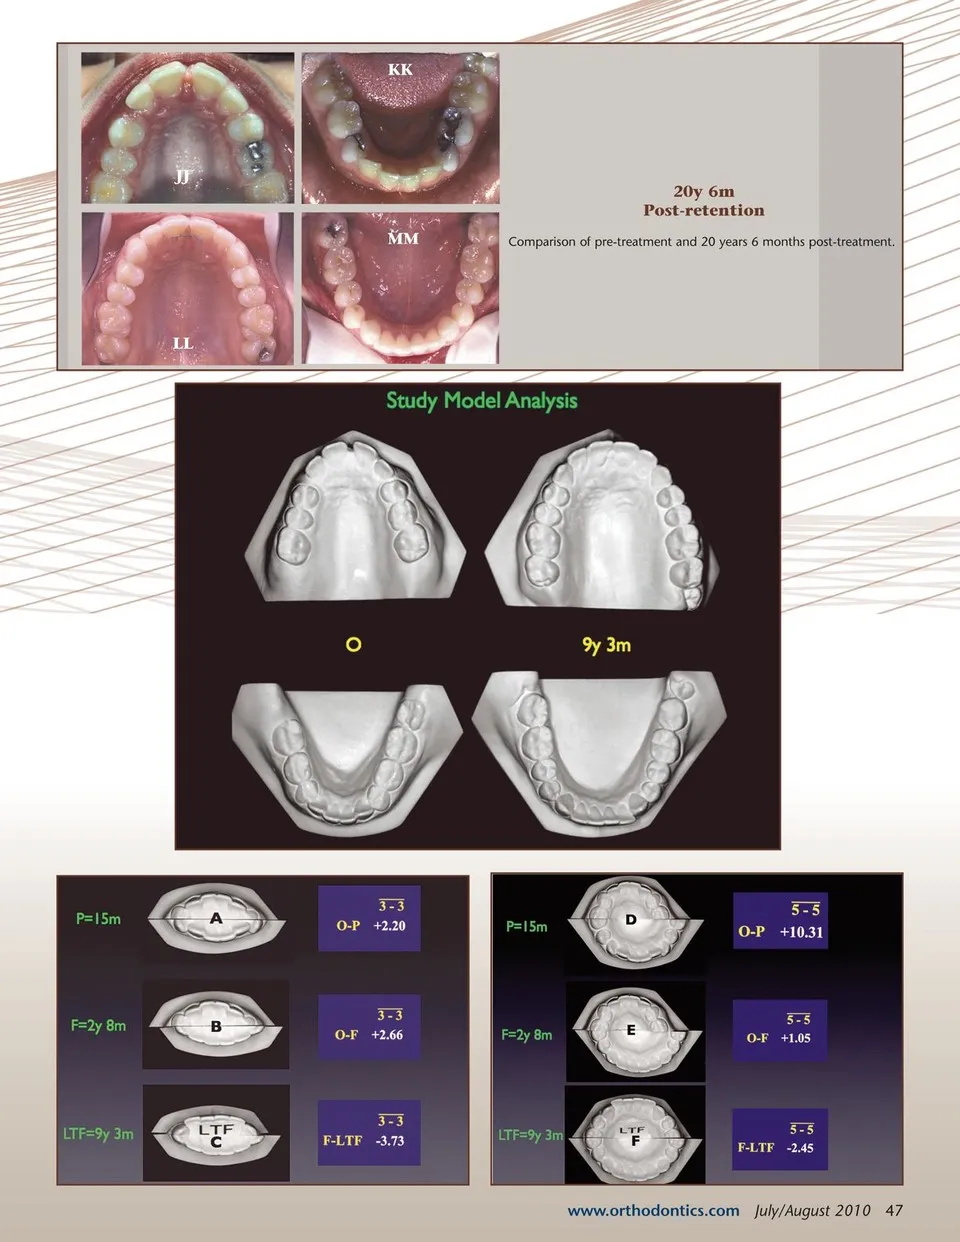

L D 15m J Treatment progression at 15 months. 30m M Treatment progression at 27 and 30 months. E K F 27m G N Y 2y 8m X AA 4y 8m Z CC 9y 3m BB Post-retention occlusal views from 2 years 8 months, 4 years 8 months and 9 years 3 months after debanding. “The essential treatment objectives were to upright and distalize all posterior segements simultaneously(i.e. coordinate upper arch and lower arch tooth movements.)” O DD 20y 6m EE FF GG 46 July/August 2010 JAOS HH II